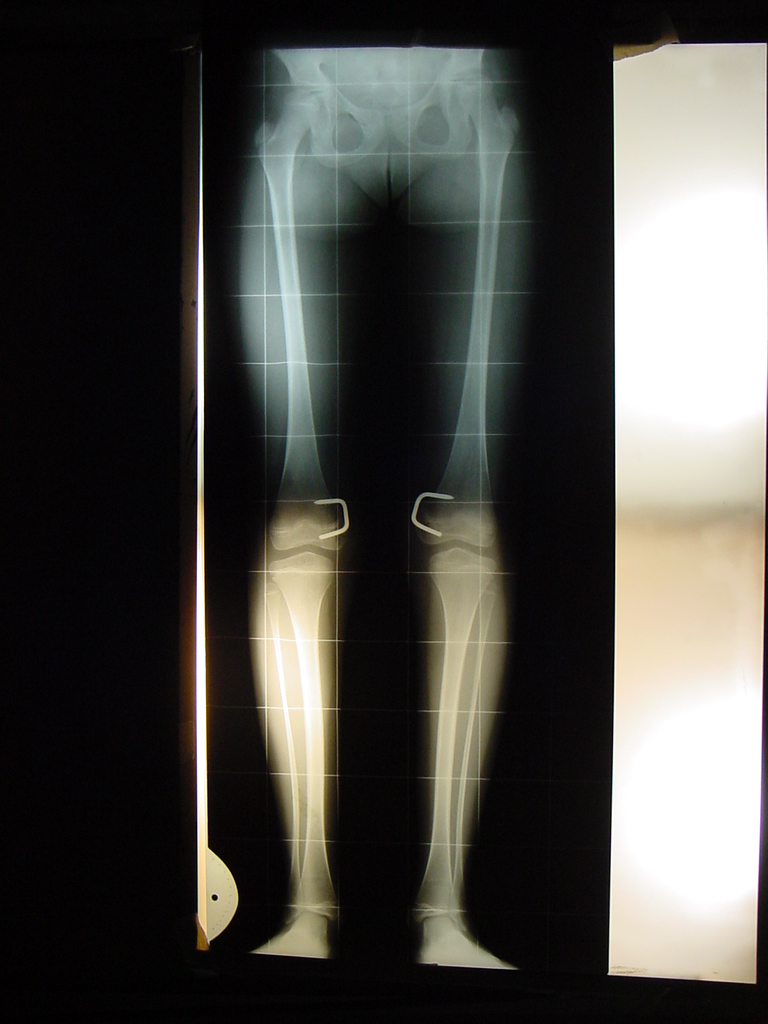

Growth Modulation in Renal Osteodystrophy